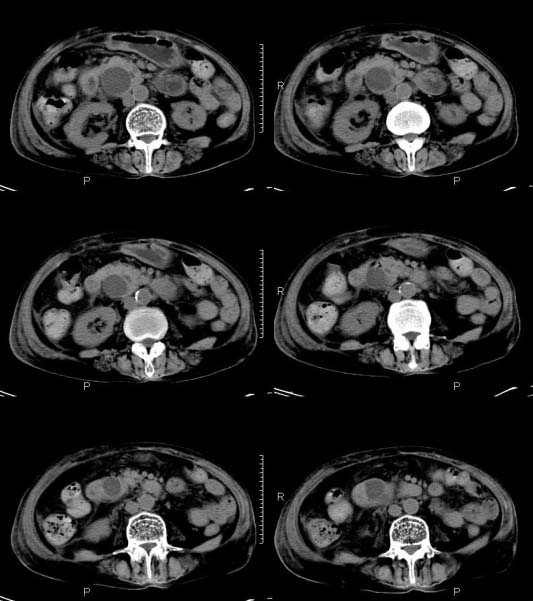

女,71岁,腹痛、腹胀、黄疸20余天,b超示肝内外胆管高度扩张内伴絮状物质(未提示梗阻部位或结石影),经抗炎解痉治疗后,肝功能有所好转,但胆道梗阻状态并未减轻。患者曾于1970年代做过胆囊切除术,1997年因胰腺炎而手术;且患者有糖尿病10余年。ct图片传了静脉期,未传动脉期了,最后一序列为3.2mm薄扫,请各位同仁仔细看看,确定一下胆管梗阻的部位,是炎性梗阻还是肿瘤性梗阻,是否与胰腺炎有关系,扩张胆总管中段前缘是否是胰管。请高手们最好用图示来指出梗阻部位。

先天性胆总管囊肿伴肝内外胆管扩张!

肝内外胆管显著扩张,考虑先天性胆管囊肿(ⅳ型)。

肝内胆管远侧、近侧不比例扩张,以近侧为明显。胆总管扩张。考虑先天性胆管囊肿(ⅳ型)。

先天性胆管扩张;未见明显肿瘤病变。